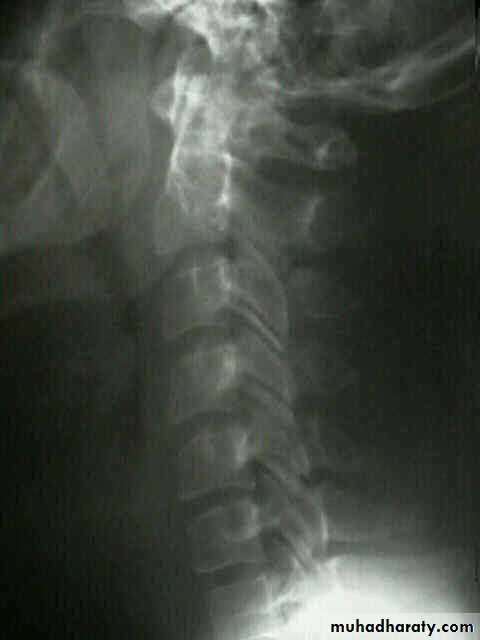

Spine injuries

Cervical classifications

wedge compression fracture of vertebral body

burst fracture of vertebral body

extension subluxation

flexion subluxation

fracture of the atlas

fracture-dislocation of the atlanto-axial joint

intraspinal displacement of soft tissue

soft-tissue strain

('whiplash injury')

injuries of the cervical spine are usually caused by indirect violence,

Such as falls on to the head or

other violent movements transmitted from the skull. i.e in any direction.

flexion,

tension, lateral flexion or

rotation-

or a vertical compression force acting on

a straight spine.

DIAGNOSISX RAY

Anterio posterior X ray radiograph.lateral radiographs with the head in flexion and extension may revealinstability that is not shown in the routine lateral film.

oblique views

at 45° are especially helpful

a special projection

through the open mouth.

Computed tomography (CT)

and magnetic resonance imaging (MRI).